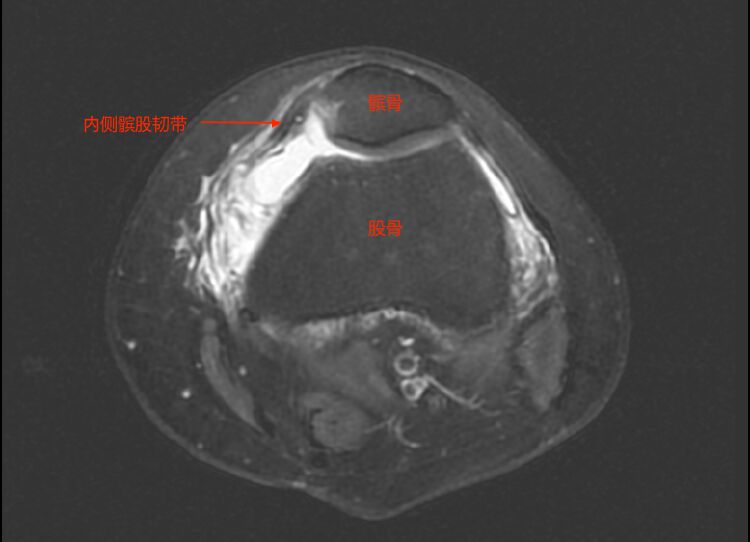

造成复发性髌骨脱位的因素众多,其中,内侧髌股韧带是导致复发性髌骨脱位的主要因素。经检查,汤女士内侧髌股韧带断裂了。

内侧髌股韧带是限制髌骨向外侧滑移的稳定结构。当此韧带损伤时,髌骨就可能发生脱位或者半脱位,引起膝关节肿胀、疼痛及活动受限,严重时还可引起髌股关节面软骨及膝关节内其它结构损伤。

▲汤女士初次受伤时左膝关节MR提示内侧髌股韧带自股骨端撕脱